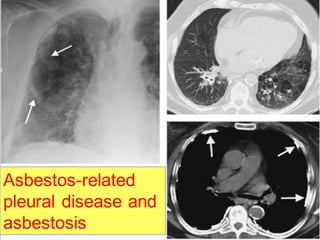

Rule no. 2

Reticulonodular lower lung predominant

distribution with decreased lung volumes

suggests: (APC)

1. Asbestosis

2. Aspiration (chronic)

3. Pulmonary fibrosis (idiopathic)

4.Collagen vascular disease

Asbestos-related

pleural disease and

asbestosis

Rule no. 5

Associated pleural thickening and/or

calcification suggest asbestosis.

• 197.

Rule no. 5 Associatedpleural thickening and/or calcification suggest asbestosis.